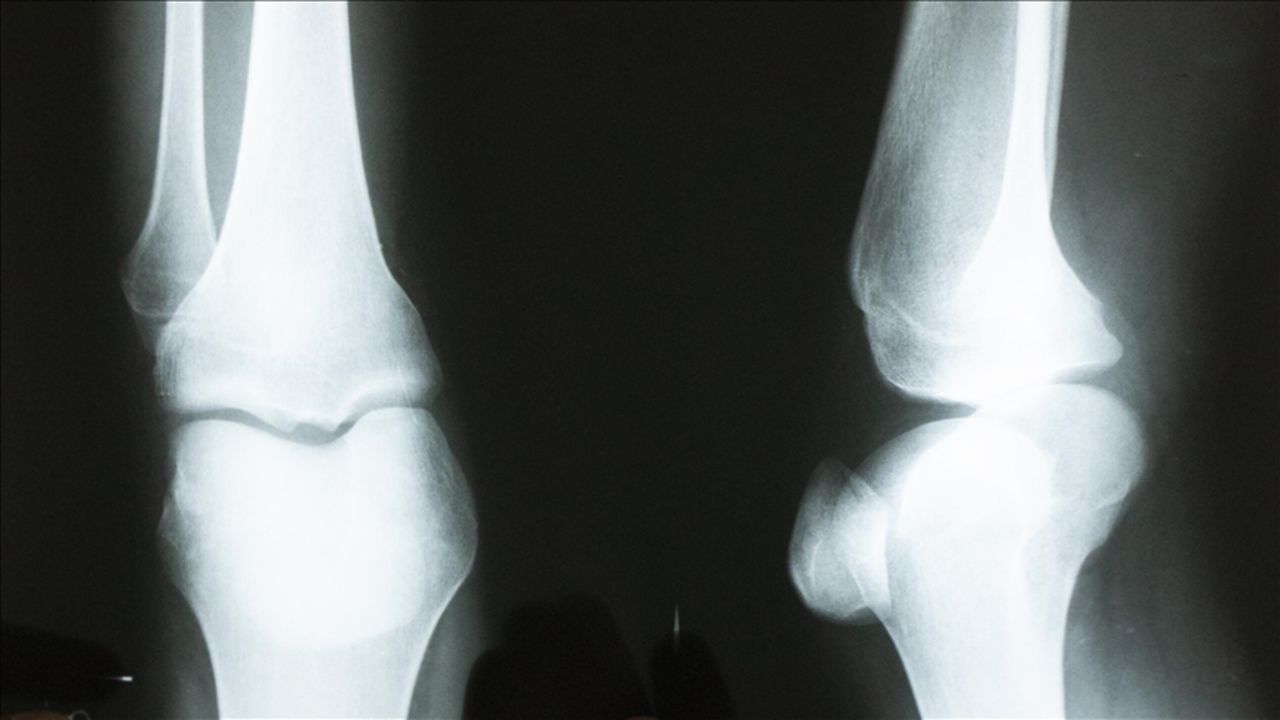

Diz kireçlenmeleri için yeni tedavi yöntemi! Düşük radyasyonla ağrılar azalacak

Osteoartrit, artritin en yaygın türü olup yalnızca ABD’de 32 milyondan fazla yetişkini etkiliyor. Kemik uçlarını kaplayan kıkırdağın zamanla aşınmasıyla oluşan bu durum; ağrı, sertlik ve günlük işlevlerde azalmayla kendini gösteriyor. Mevcut tedaviler hayat tarzı değişikliklerinden ağrı kesicilere, ileri aşamalarda ise eklem protezi cerrahisine kadar uzanıyor.